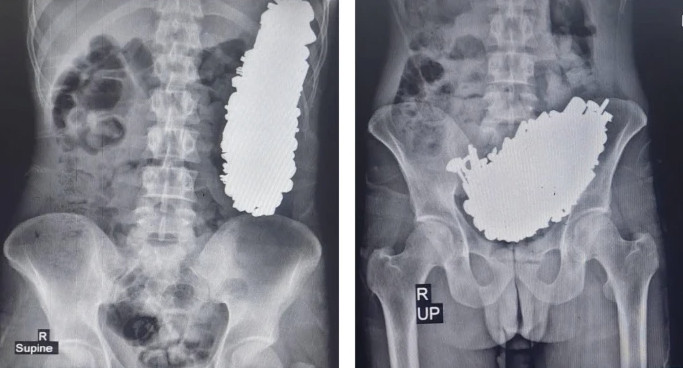

Άμεσα υπέβαλαν σε ακτινογραφία τον ασθενή όπου είδαν το στομάχι του γεμάτο με μεταλλικά αντικείμενα, τα οποία είχαν προκαλέσει απόφραξη της γαστρικής εξόδου.

Ο ασθενής υποβλήθηκε σε επέμβαση γαστροστομίας και αφαιρέθηκαν από το στομάχι συνολικά 452 μέταλλα, μεταξύ των οποίων βίδες, παξιμάδια, κλειδιά, πέτρες και άλλα μεταλλικά μέρη βάρους 3 κιλών!